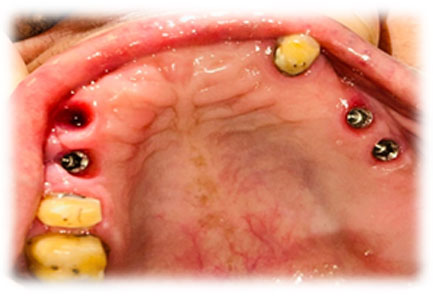

At PDC DENTAL CLINIC: Super Speciality Dental Practice in Vadodara, Gujarat, we specialize in Guided Implant Surgery, a cutting-edge dental service designed to ensure precision and optimal outcomes for our patients. Our clinic leverages the latest technology in dental implantology, offering a minimally invasive approach that enhances accuracy, reduces recovery time, and ensures a high success rate.

Guided Implant Surgery involves the use of advanced 3D imaging and computer-aided design (CAD) to plan the exact placement of dental implants. This meticulous planning process allows our dental specialists to visualize the patient’s oral anatomy in great detail, ensuring the implants are placed in the most ideal position for both functionality and aesthetics. The procedure is tailored to each patient's unique needs, ensuring a personalized treatment plan.

These technique assures that the implant is precisely placed without any damage to nerves, vessels and wouldn't perforate maxillary sinus too.